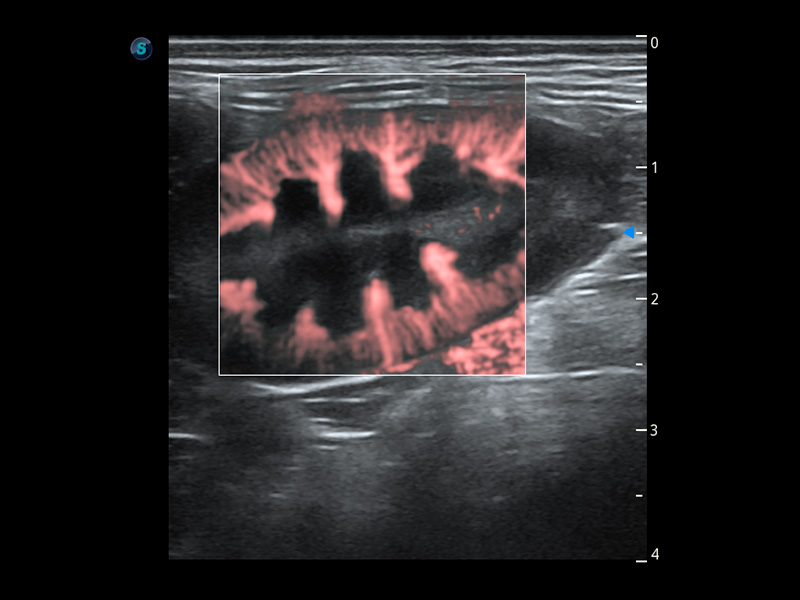

ProPet 60 作为一款高端台式动物超声设备,为动物医生的日常诊断提供了一系列贴合动物临床需求、解决临床实际问题的高级成像功能。凭借全系列高清探头,满足医生对腹部、心脏、生殖、浅表、肌骨等成像的所有需求,切实帮助您提升检查效率,提高诊断信心。

动物是人类最亲密的朋友和最值得信赖的伙伴。1xBET也一直致力于探索动物专用的超声影像解决方案。 全新推出的ProPet系列,是1xBET在动物超声影像智能化、专业化、精准化的一次跨越式革新。动物不能用言语来表述自己的不适,通过超声影像,ProPet系列搭建了动物医生与不同物种沟通的“桥梁”,为动物医生注入了“治愈之力”。